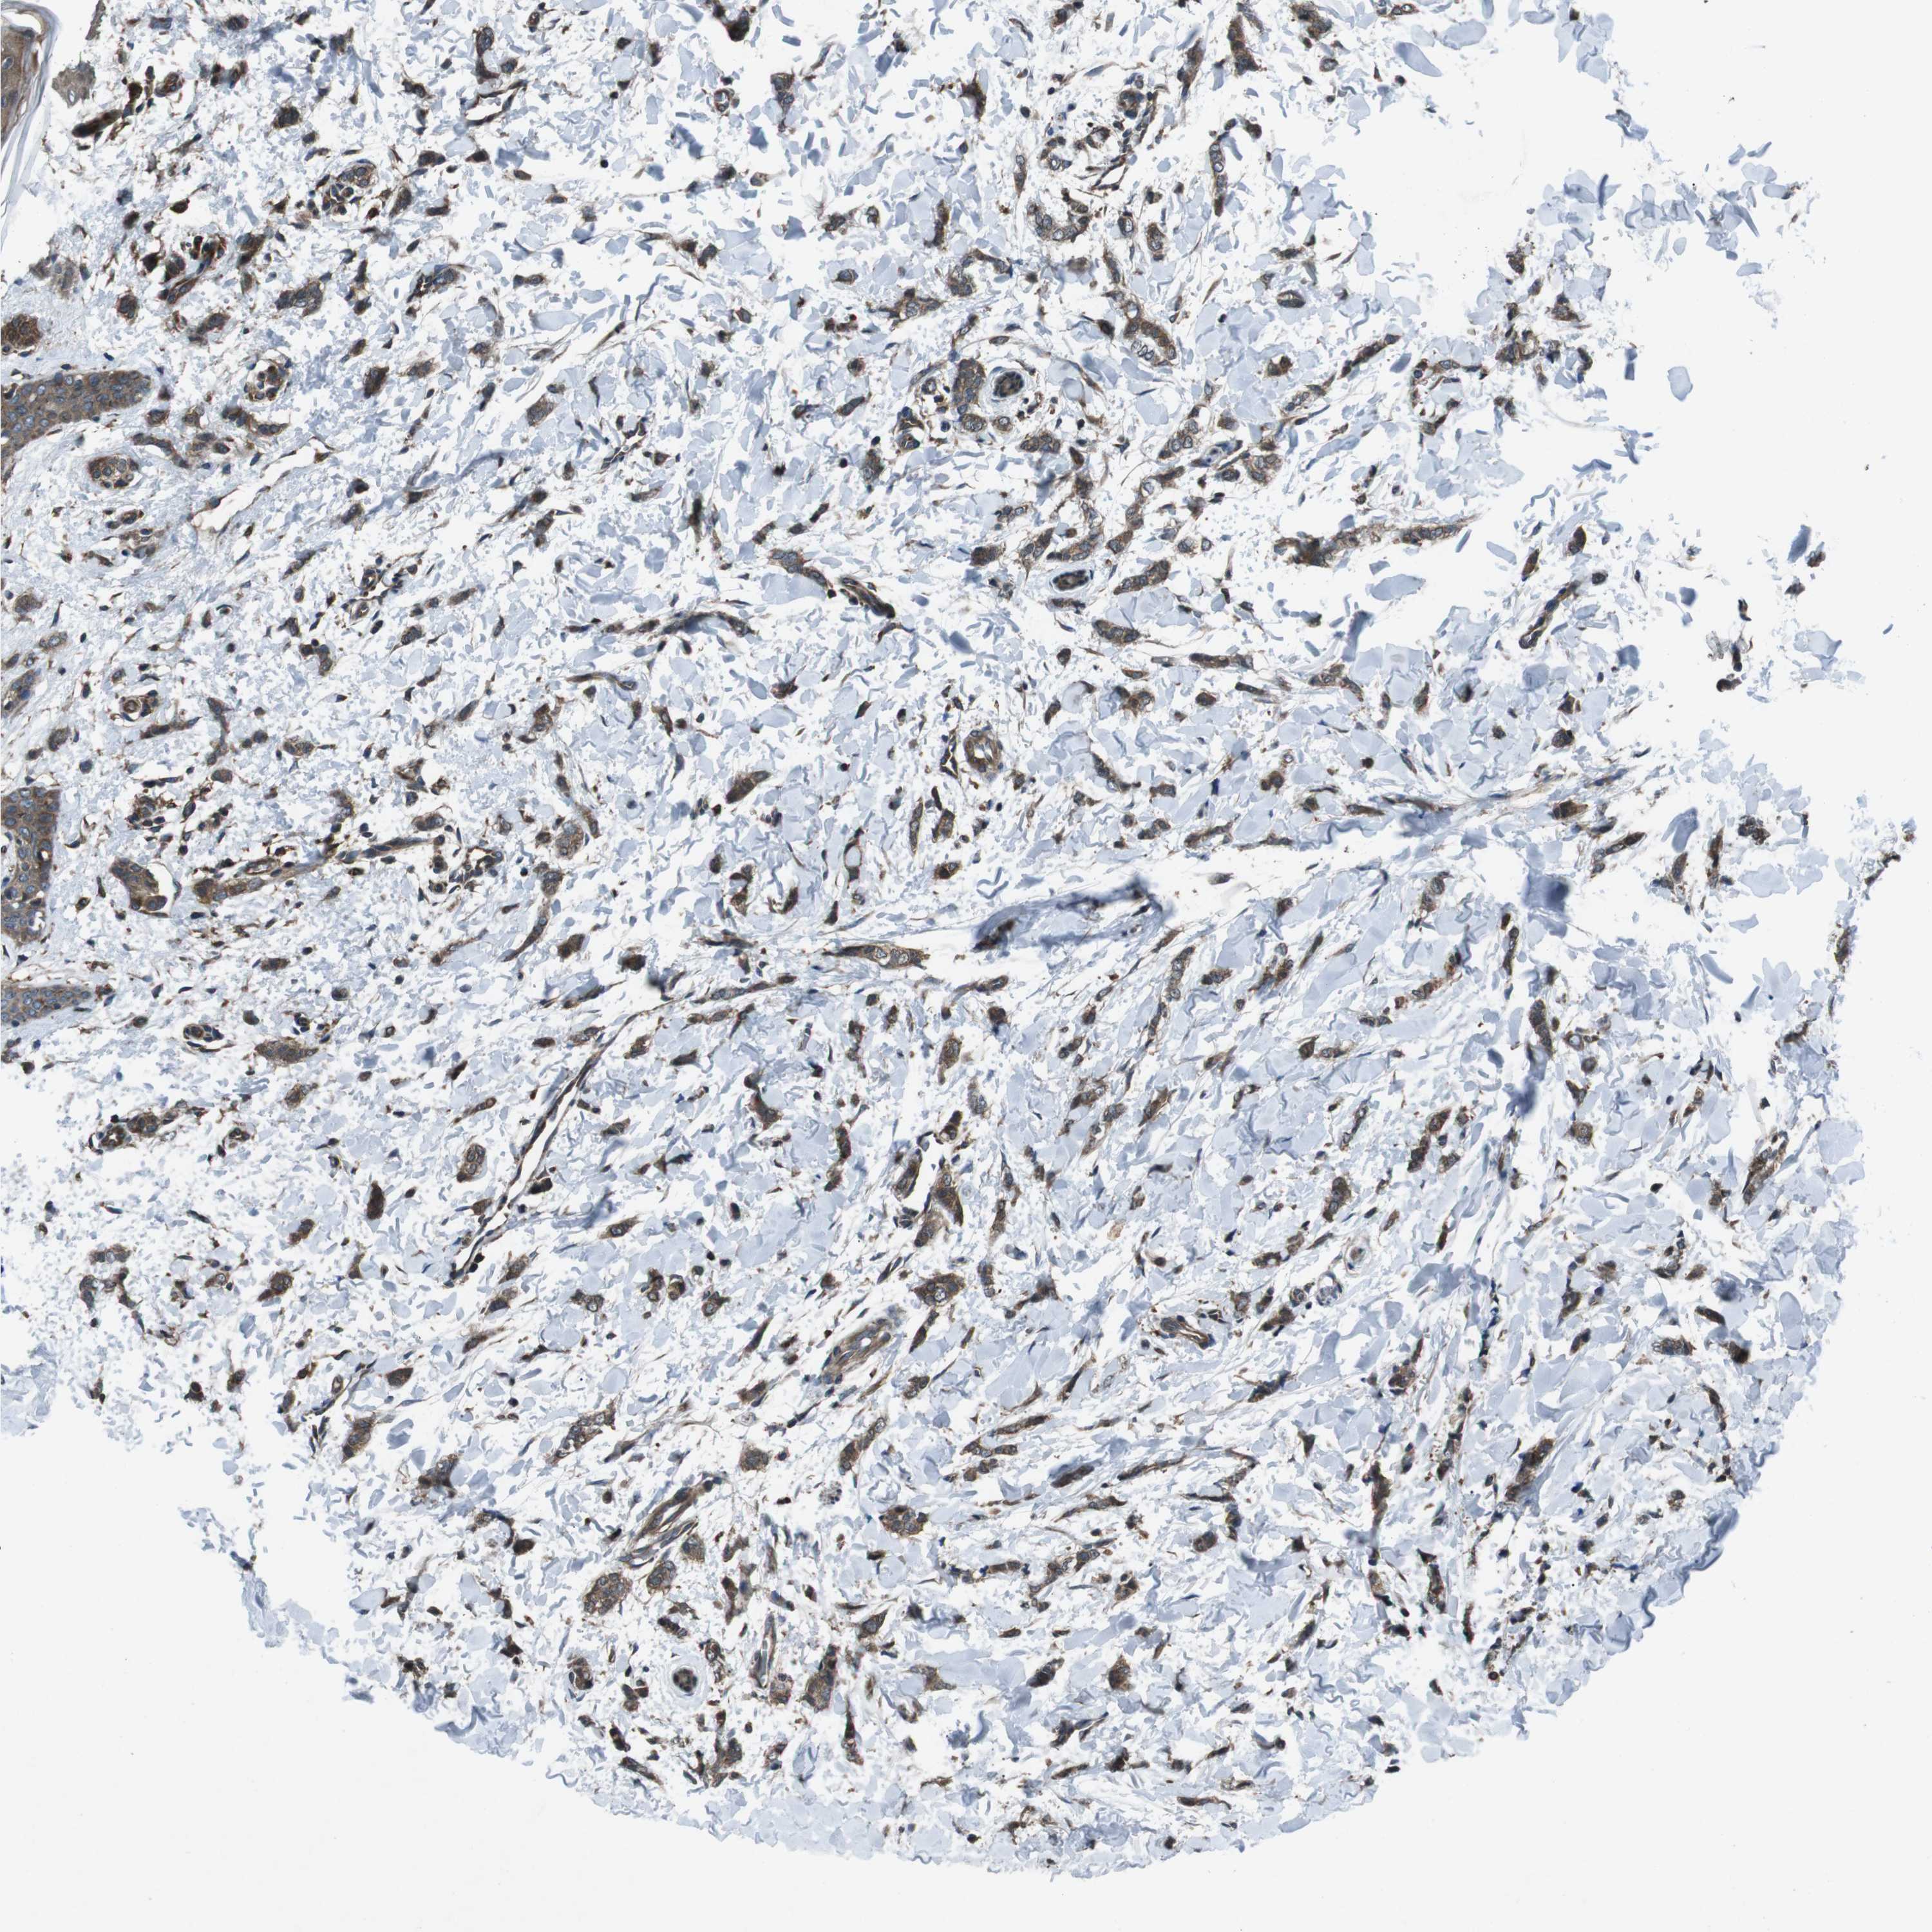

CANCER BREAST CANCER Show tissue menu

BRCA TCGA BRCA VALIDATION PROTEIN EXPRESSION